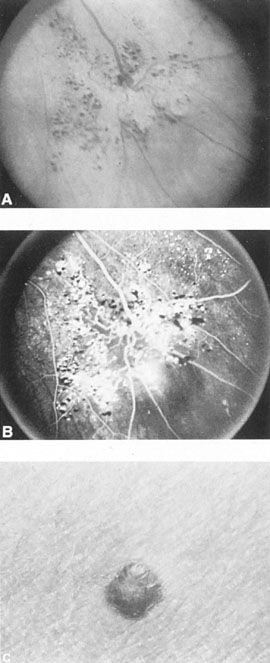

SUPRATENTORIAL

From 85% to 90% of AVMs are in the supratentorial compartment and are supplied primarily by the carotid circulation (Figs. 7 and 8). The remainder are supplied by the vertebrobasilar system. The approximate frequency of location is as follows: frontal, 22%; temporal, 18%; parietal, 27%; occipital, 5%; and deep intraventricular or paraventricular, 18%. The intracerebral site of the malformation does not necessarily indicate that there will be signs referable to that area simply from the mass effect of the malformation. Clinical features primarily result from subarachnoid hemorrhage or intraparenchymal hemorrhage with hematoma formation.

Fig. 7. Supratentorial arteriovenous malformation in a 28-year-old woman with a history of focal motor seizures for many years and a recent subarachnoid hemorrhage. A: Lateral projection carotid arteriogram demonstrating a huge deep hemispheral arteriovenous malformation. B: Frontal projection. C: Fundus photograph showing anomalous tortuous vasculature in each eye. No retinal arteriovenous shunt was detectable.

Fig. 8. Multiple supratentorial arteriovenous malformations (AVMs). A: Lateral projection of left carotid arteriogram shows dilated afferent artery (solid arrow) feeding the right hemispheric parietal AVM (open arrow). B: Right carotid injection fills a second, more posteriorly located, parietooccipital AVM (open arrow), which drains immediately to markedly dilated cortical veins (curved arrow).

In general, when hemorrhage occurs involving a portion of the visual radiations, a homonymous visual field defect is to be expected. Selective involvement of the anterior visual pathways may occur either with extensive venous angiomas at the base of the brain or as part of the Wyburn-Mason syndrome (see later), with direct involvement of the optic nerve, chiasm, or tract. Other variants such as congenital cavernous hemangiomas may involve the anterior visual pathways,68 as may intraparenchymal cryptic AVMs69 and present as symptomatic visual loss also resulting from hemorrhage and hematoma. Amaurosis fugax may even be the presenting symptom of supratentorial AVMs when blood is shunted to the meningeal circulation from the ophthalmic artery.70 When supratentorial AVMs drain into dural venous sinuses or the vein of Galen, distant ocular effects evolve, such as proptosis71 or ophthalmoplegia72 because of arterialization of cavernous sinus complex.

Of particular interest are those AVMs that involve the occipital lobe (Fig. 9). The clinical differentiation of migraine from a cerebral AVM was previously regarded as difficult because the clinical features of occipital lobe AVMs include visual phenomena or headaches. However, in most cases the clinical distinction is possible. In 26 cases with occipital AVM, two distinct syndromes were defined in 18 patients: occipital epilepsy and occipital apoplexy.73 Focal seizures with occipital malformations consist of elementary visual sensations similar to the phenomena evoked by direct cortical stimulations. When seizure activity occurs in the striate cortex (area 17), the patient usually reports sensations of moving lights in the right or left homonymous fields. The sensations are poorly formed, episodic, usually brief, sometimes colored, and unassociated with the angular, scintillating figures so characteristic of migrainous cortical phenomena. Epileptic discharges from areas 18 and 19 cause photopsias that are unlikely to remain stationary and to flicker rapidly. The epileptic photopsias usually last only seconds; occasionally they last for a few minutes before the onset of a generalized seizure. In other instances only the brief visual episodes occur without spreading to produce a generalized seizure. Momentary dimming or blindness in one or both homonymous fields may be experienced with seizure activity in the occipital areas.

Fig. 9. Carotid arteriogram of an occipital lobe arteriovenous malformation (AVM). Lateral (A) and frontal (B) projections demonstrating a small occipital AVM (arrow). The patient was a 23-year-old woman who presented with severe apoplectic unilateral headache, total left homonymous hemianopia, and mild nuchal rigidity. Despite xanthochromic cerebrospinal fluid, she was initially diagnosed elsewhere as having migraine. An AVM was successfully resected, and a small occipital lobe hematoma was removed.